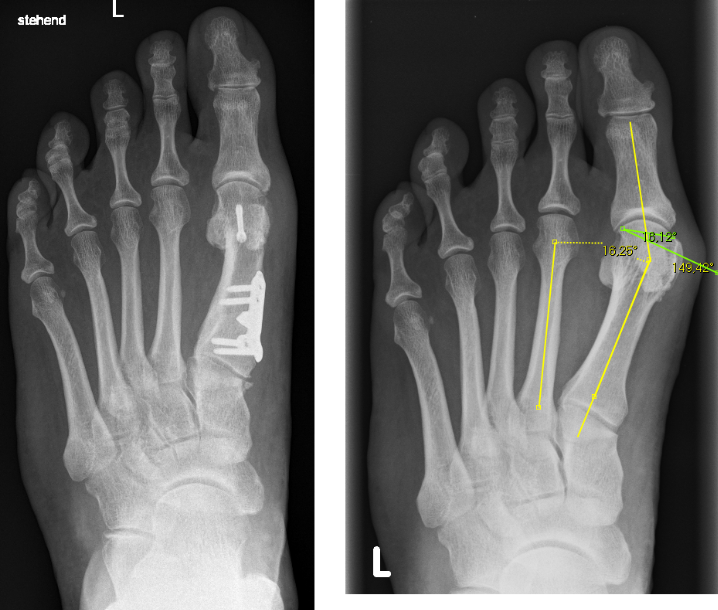

Gesamtes Spektrum der Fuß und Sprunggelenkchirurgie (Plattfuß, Spreizfuß, komplexe Vor-, Mittel- und Rückfußkorrektur, Krallenzehen und Hallux valgus/rigidus, Morton Neurinom)